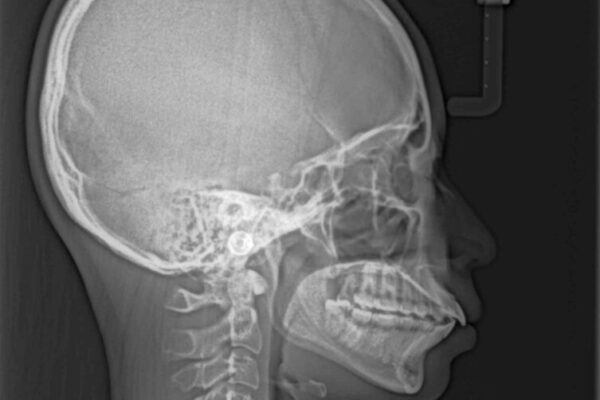

上下の前歯が突出しており、口が閉じにくいとのことで来院された患者様です。

上下前歯が著しく前突している状態であったので、上下左右の第1小臼歯4本を抜歯し、ワイヤー装置にて矯正治療を行うこととしました。

舌の突出癖により、前突になったと考えられたため、舌のトレーニングをしっかりと行うよう指導しました。